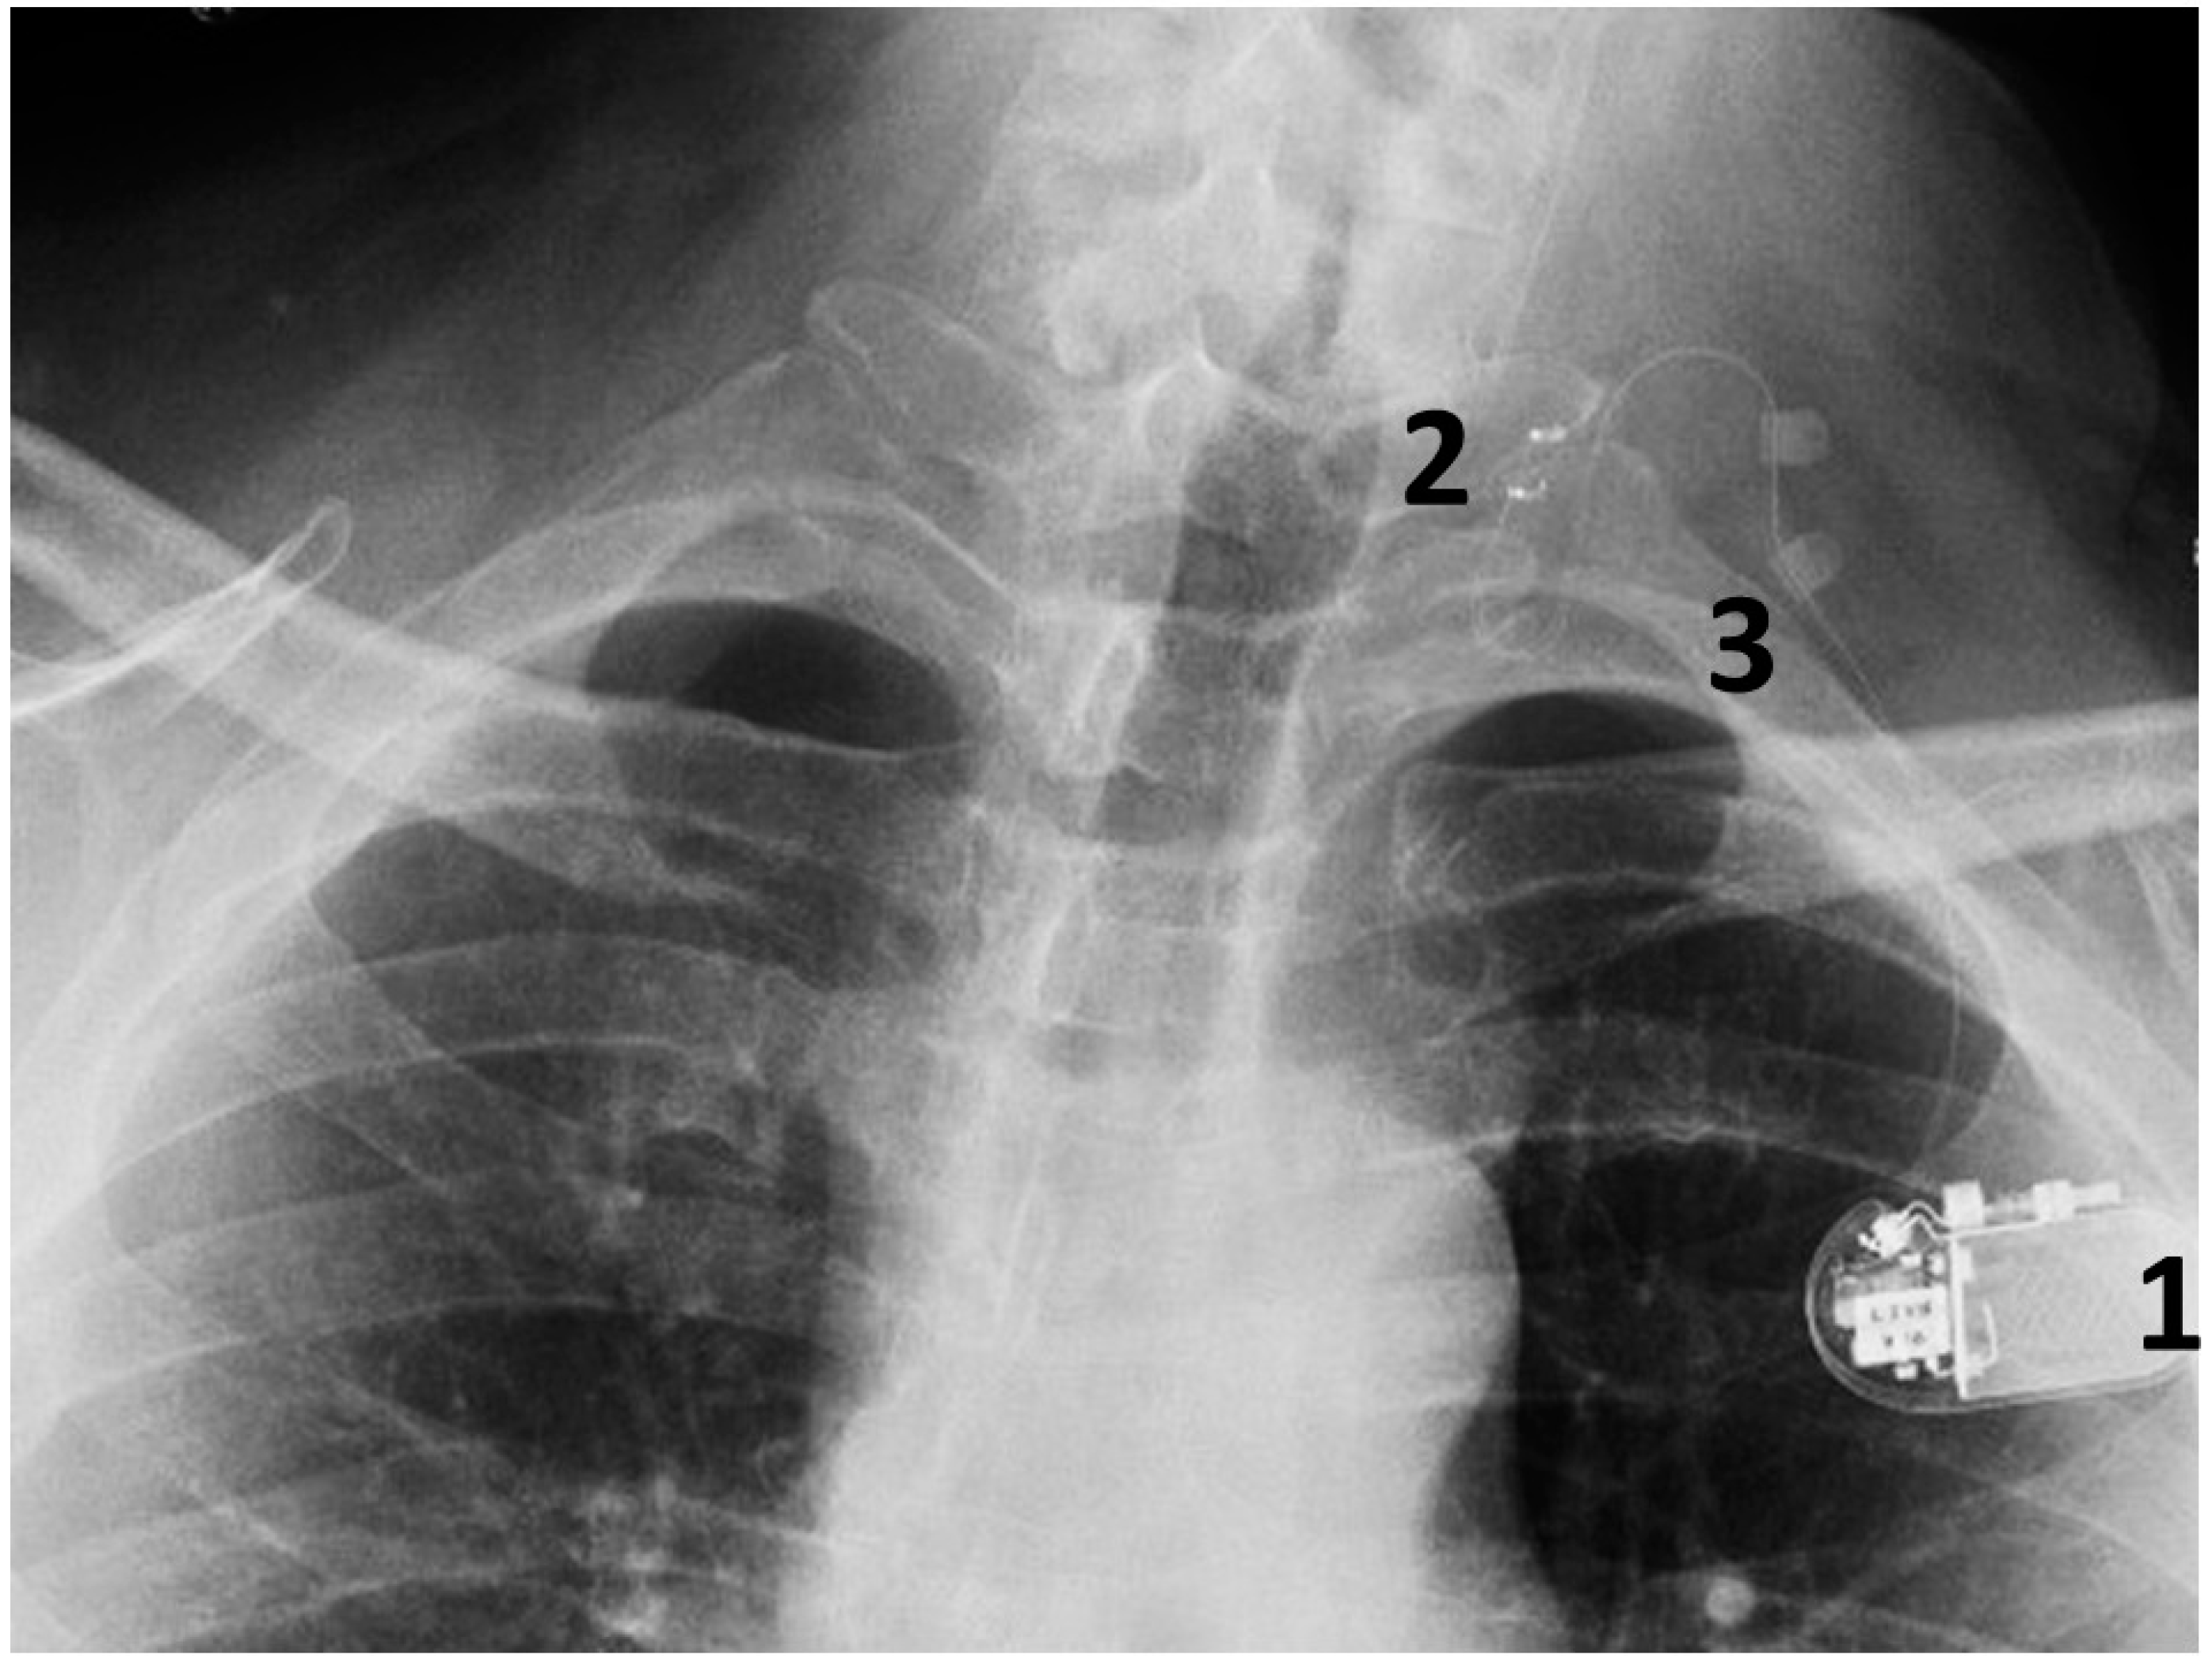

Figure 4.

A chest radiograph showing the components of the implanted VNS system: 1. The implantable pulse generator; 2. the electrode contacts on the left vagus nerve; 3. silicone anchors to stabilize the electrode in place.